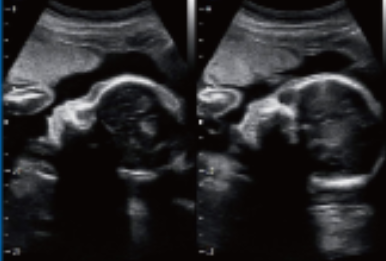

Примеры изображений:

Визуализация плода, 2В-режим

Визуализация плода, 2В-режим